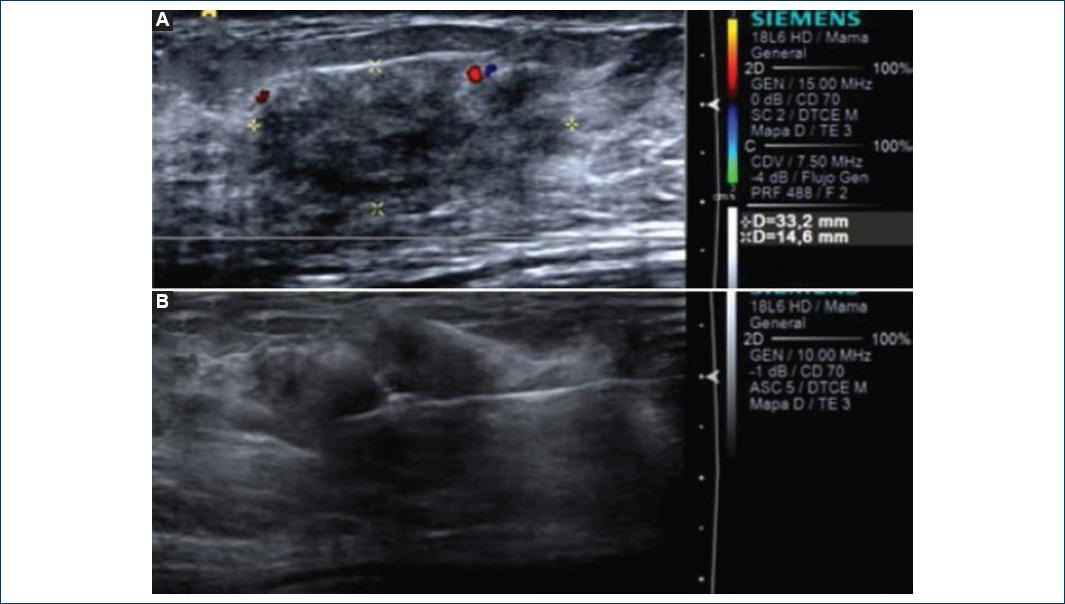

We report a 42-year-old woman with a long history of T1D with diabetic neuropathy. She came to our center because of an enlarging left breast mass. Clinical examination showed a left breast mass with nipple retraction. Mastography and ultrasound revealed a left breast BI-RADS-4c lesion (Figs. 3 and 4). Ultrasound-guided biopsy was performed, and after pathology study, DM was diagnosed.

Figure 4 Diabetic Mastopathy. A, B: breast ultrasound: irregular mass with angular margin, posterior shadowing, and parallel orientation color Doppler showing no vascular flow within the mass; C: percutaneous breast biopsy.